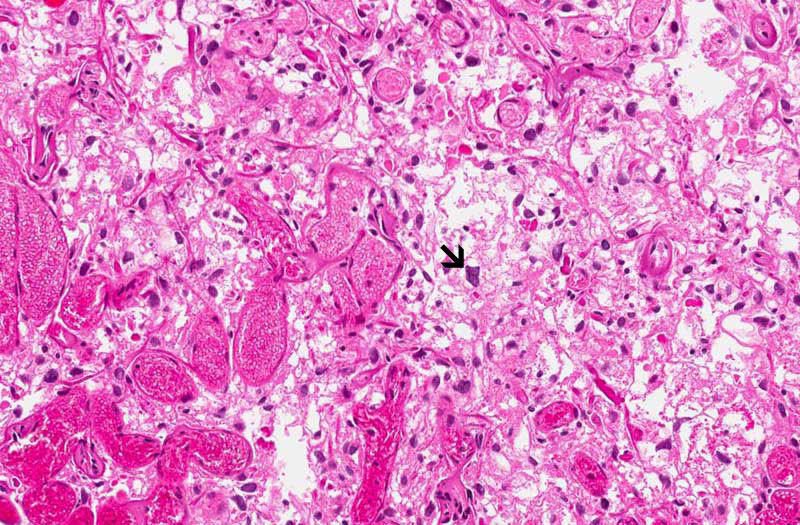

Slide #1 represent the tissue that are

received at the time of frozen. Only half of the tissue was

submitted for frozen and the slide being shown here represents the

portion that have not been frozen. This specimen appears to be a

highly vascular lesion with quite a good amount of stromal cells in

between (area 1 and 2). Note that the stromal cells have

hyperchromatic nuclei but no prominent nucleoli. There are no

intranuclear inclusions or high grade pleomorphism. No definitive

clear cells were observed. Definitive sclerotic changes are present

in many of the blood vessels.